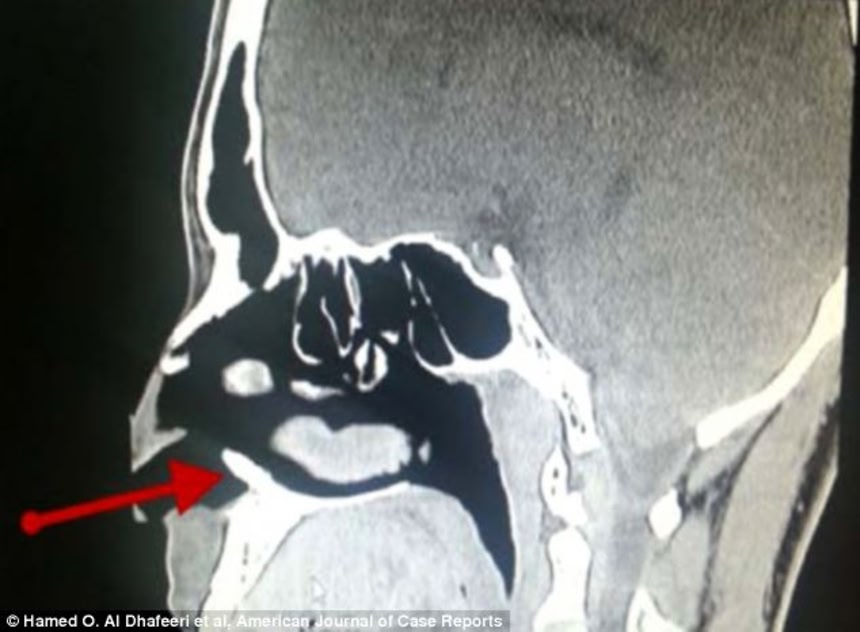

この驚きのエピソードを持つ人は22歳のサウジアラビアの男性で、一ヶ月の間に1~2回起こる鼻血に3年もの間苦しめられていた。医者が患者の診察で発見したのは、約1センチの象牙色をした骨状の物だった。

この画像を大きなサイズで見る医師は歯科医の同僚と意見を交え、結果的に骨の正体は「余分に生えてきた歯だと思われる」と結論づけた。ちなみに患者の口内に存在する歯は完全に生え揃っており、本数も揃っていたそうだ。

レントゲンじゃなくてCT像じゃないかな…

それとこれはCT画像ね。